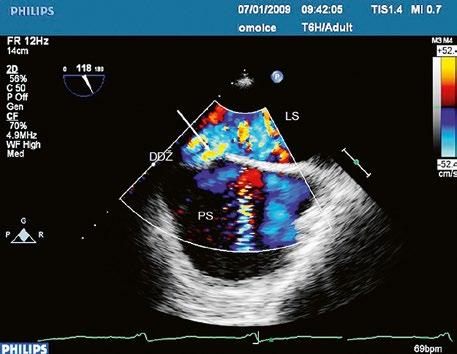

Obr. 45.4 Defekt typu sinus venosus superior s levopravým zkratem v barevném dopplerovském mapování. TEE v longitudinální projekci, defekt se nachází v horní části septa, je označen žlutou šipkou, na něj nasedá horní dutá žíla (HDŽ)

AP – plicnice, LS – levá síň, PS – pravá síň

z Defekt síňového septa typu sinus venosus superior: 9 %, v místě vústění horní duté žíly (HDŽ), která na defekt nasedá, téměř vždy je spojen s parciálním anomálním návratem pravostranných plicních žil do HDŽ nebo do pravé síně (kap. 45.18 Anomální návrat plicních žil (Obr. 45.3, Obr. 45.4, Video 45.3, Video 45.4).